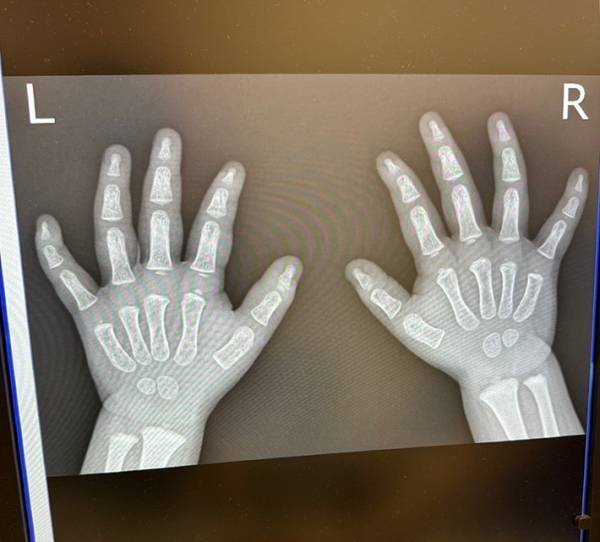

病院で息子の手のレントゲンを撮ったら?

ココ3(@shonancoco3)さんはある日、手を痛めた1歳の息子さんを病院に連れて行ったといいます。

骨折などの可能性を考え、医師は両手のレントゲンを撮影。場合によっては、重大なケガが判明する可能性もあるため、ココ3さんは気が気でなかったでしょう。

…しかし、その後写っていたモノを見た医師とココ3さんは、笑い合う事態に!

理由が分かる、実際のレントゲン写真をご覧ください。

か、かわいすぎる!

そこには発達途中の骨がはっきりと写っており、レントゲン写真ではあるものの、ムチッとした肉感が伝わってきます…。

我が子のかわいさを熟知しているココ3さんでも、骨格までかわいいとは驚いたことでしょう。なおさら、愛おしさがこみ上げますね!

幸い、息子さんは大事には至らなかったようです。